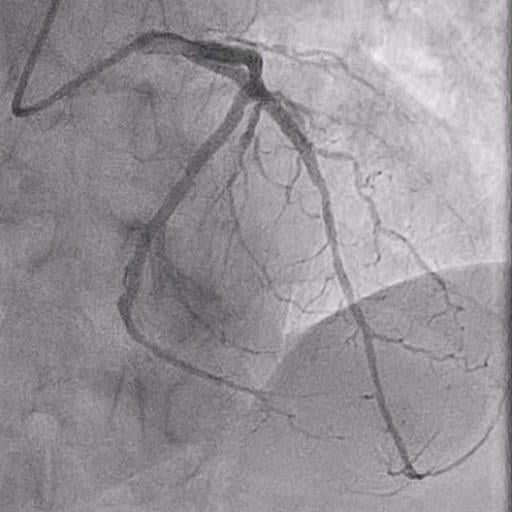

Figure 3: DCB inflation

Once a satisfactory result is achieved in lesion preparation (similar to stent-like outcomes), DCB angioplasty can be performed.

It is essential to handle the device carefully during preparation, avoiding contact with the balloon surface to prevent drug loss.

After positioning the device at the target lesion, inflate it to 6-8 ATM and maintain inflation for at least 1 minute.

In this case, a sirolimus drug-coated balloon catheter 3.0 x2 5mm was inflated for 1 min at 10 ATM.

If chest pain or ST-segment changes arise, consider performing two inflations of 30 seconds each, rather than a single inflation.

It's important to note that the DCB angioplasty phase is intended only for drug delivery, not for lesion dilation.

Therefore, the device should not be inflated at high pressures for dilating the lesion.